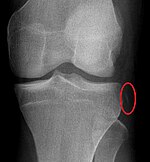

Segond fracture Paul Segond lateral tibial plateau avulsion fracture with anterior cruciate ligament tear Segond fracture at Who Named It? SegondFracture.JPG